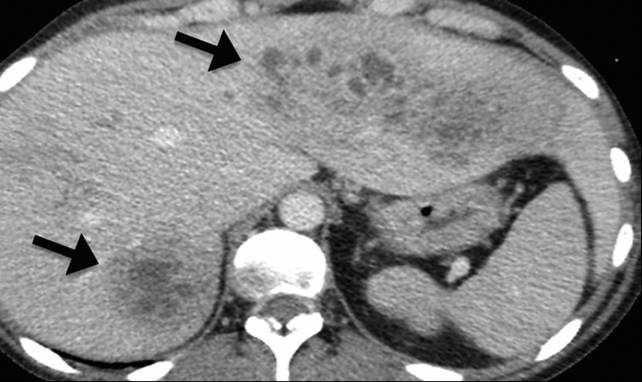

Hình 1